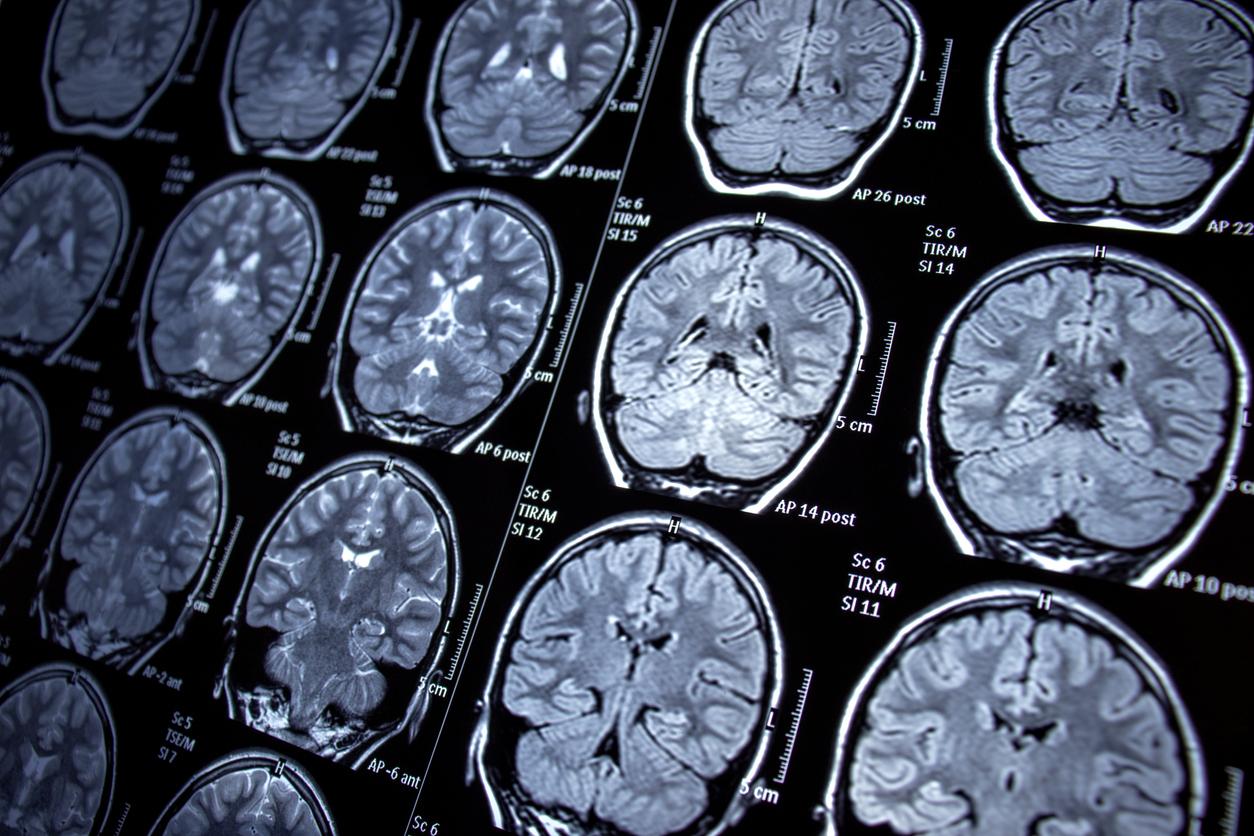

Des chercheurs ont voulu comprendre les régions du cerveau impliquées dans plusieurs de ces troubles mentaux. Ils en ont isolé six : la dépression, l’anxiété, la schizophrénie, le trouble bipolaire, la toxicomanie et le trouble obsessionnel compulsif (TOC).

Pour les étudier, ils ont analysé les données cérébrales de 15.000 personnes. Parmi elles, certaines ne souffraient pas de maladie mentale et d’autres en présentaient. Leurs résultats sont publiés dans la revue Nature Human Behavior.

Chez ceux qui avaient des troubles mentaux, certaines zones du cerveau étaient touchées. Il s’agit de la cingulaire antérieure, une région associée aux émotions, et de l’insula, une zone liée à la conscience de soi. Dedans, la matière grise était diminuée. Néanmoins, ces régions du cerveau sont aussi affectées par les maladies neurodégénératives.

Pour mieux comprendre la façon dont les troubles mentaux touchent spécifiquement le cerveau, ils ont analysé le connectome, une carte existante des connexions cérébrales humaines. Ainsi, ils ont découvert un réseau spécifique aux diminutions de matière grise, commun à tous les diagnostics de maladies mentales, c’est le réseau transdiagnostique. Ce n’est donc pas le résultat de la diminution de la matière grise qui importerait pour les maladies mentales mais plutôt le chemin pris par cette altération.